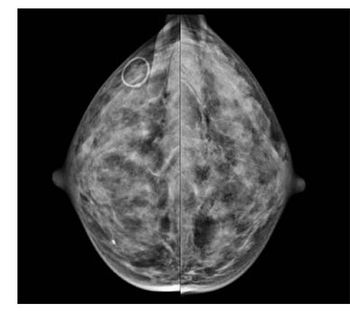

Digital mammography may be feasible using low-dose radiation dose techniques.

Did false-positive mammograms deter women from undergoing future breast cancer screening per guidelines?